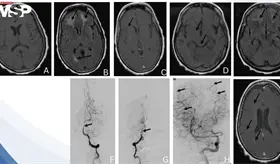

El accidente cerebrovascular isquémico puede anunciarse días antes de ocurrir. Conocer sus señales de alerta y adoptar hábitos preventivos puede marcar la diferencia entre la vida y la muerte.